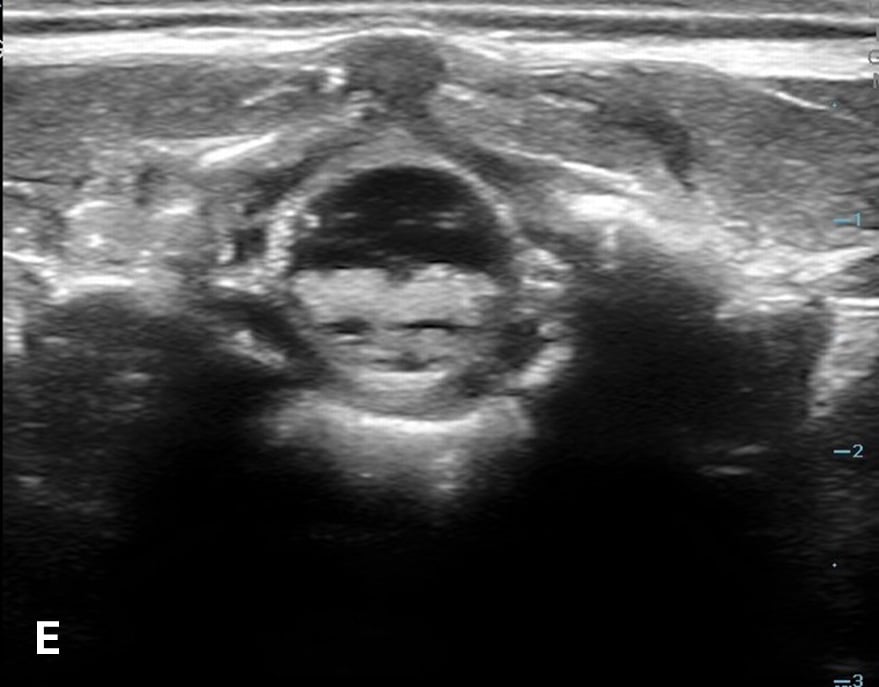

The transverse view should also be obtained to verify landmarks and identify any overlying vessels or hematomas (from prior attempts) to avoid. The transducer is rotated to the transverse position on the lower back and moved caudally over the spinous processes to locate the CM, which is a hypoechoic structure positioned in the center of the spinal canal. At higher levels of the CM, the ventral roots and dorsal roots can be identified, which are surrounded by the anechoic CSF. Next, gradually move the transducer caudally and observe the CM decreasing in size while being encircled by the hyperechoic fibers of the CE. (Figure 2) Once this sonographic landmark is identified, locate the center of the transducer and mark the corresponding area on the skin, aligning it with the center of the spinal cord. Subsequently, draw lines from both markers in both planes and utilize the point of intersection as a guide for inserting the LP needle. To enhance visualization of the spinal cord’s vascular supply, and avoid a space with any overlying vessels that may cause a traumatic tap, it is advisable to apply color Doppler in both the sagittal/longitudinal and transverse views.9 (Figure 3)

Figure 2 - Corresponding US image showing spinal canal structures in transverse view:

Figure 2 - Corresponding US image showing spinal canal structures in transverse view. 2A-B: The caudal portion of the transverse view shows DR (dorsal roots), VR (ventral roots), CSF (cerebrospinal fluid), and CM (conus medullaris). 2C-D: The probe is moved caudally demonstrating the tapered CM (orange dotted circle), CE (cauda equina, hyperechoic structure surrounding the CM) and a pocket of CSF. 2E-F: Demonstrate the disappearance of the CM, and the pocket of CSF becoming larger as the probe was moved caudally. The blue circle is the entire dural sac encircling the spinal canal.